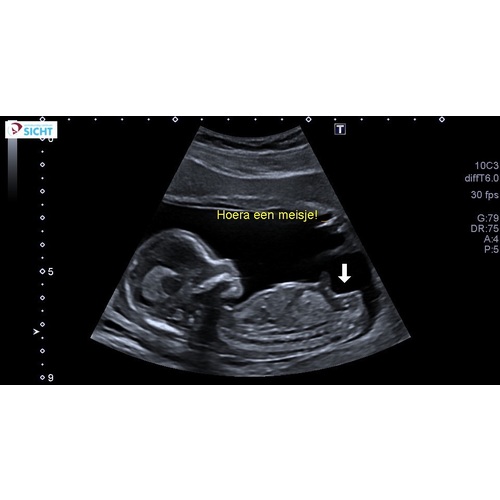

Bij mij ging ze ook meteen voor het zij aanzicht. De echoscopiste zei meteen dan kan ik het het beste meteen zien. Is een meisje. Mijnes is wel gedaan vandaag op 16+2 Dus is zeker geen nub meer. Ze zei dat dat witte staafje een schaambeen/bot is en dat bij jongetjes daarboven heel duidelijk een piemeltje met balletjes had gezeten. Daarna nog wat shots van onder gezien en ook daar was echt 0,0 te zien aan een uitsteeksel 🤣 maar zij pakte dus ook niet een pottyshot om het te zien...